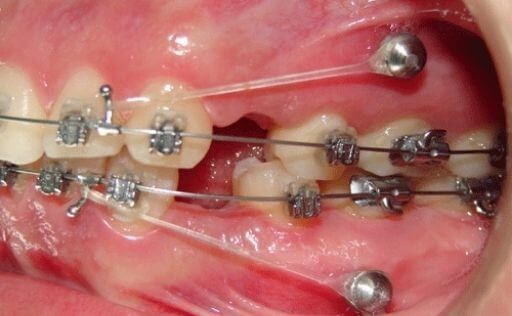

Los ortoimplantes (mini implantes para ortodoncia) son pequeños “tornillos” de fijación temporal que se colocan anclados en el hueso durante el tratamiento de ortodoncia. Estos implantes permiten que el especialista realice casi todos los movimientos dentales sin que la fuerza ejercida recaiga sobre los dientes, lo que optimiza el tiempo de tratamiento y reduce el número de aparatos utilizados en la boca. Al finalizar el tratamiento, los ortoimplantes se retiran sin dejar secuelas.

Los ortoimplantes ofrecen una solución eficaz y cómoda para los pacientes, permitiendo realizar movimientos dentales más rápidos y efectivos sin comprometer la estética. Además, al usarse menos aparatos fijos, la experiencia del tratamiento es más cómoda y menos invasiva.

Colocación y retiro de ortoimplantes